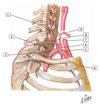

Q

A

24

2

2 - costocervical trunk

#3

26

#4 - internal thoracic artery

#5

28

#6 - thyrocervical trunk

#7

30

#8 - transverse cervical artery

#9

31